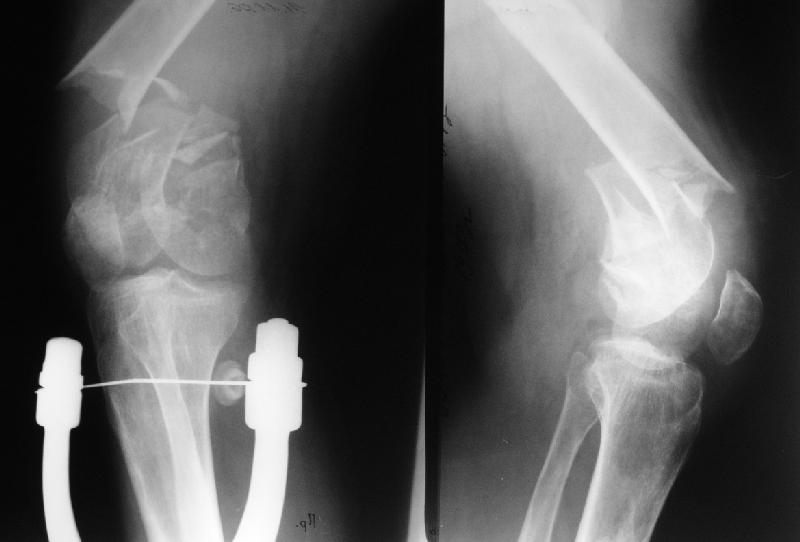

Недавно привезли на заочную консультацию рентгенграмму мужчины 33 лет. Перелом мыщелков бедра, см. снимок 1.

Смутил остеопороз. Попросили на всякий случай сделать снимок остальной части бедра. Через 2 недели привезли второй снимок - тоже приложен. Пациента уже пригласили на госпитализацию, но по поводу плана лечения пока определенности нет.

Понятно, что надо 1)остеосинтез делать, 2)исправлять деформацию диафиза и, 3)видимо, эндопротезировать тазобедреный сустав. А как и в какой очередности? Спасибо заранее за предложения.

Recently an x-ray of a male 33 y.o. from a rural hspital was presented for advice (image 1) - more or less common distal femoral fracture. But was confused by osteoporosis so requested a film with the rest of the femur. The film was just delivered - see image 2.

The patient is included to waiting list for transfer to our unit but the management program is still uncertain. Sure the distal femur requires fixation, the shaft should be aligned, and total hip performed. But what is the optimal implant(s) and order of actions? THX in advance.